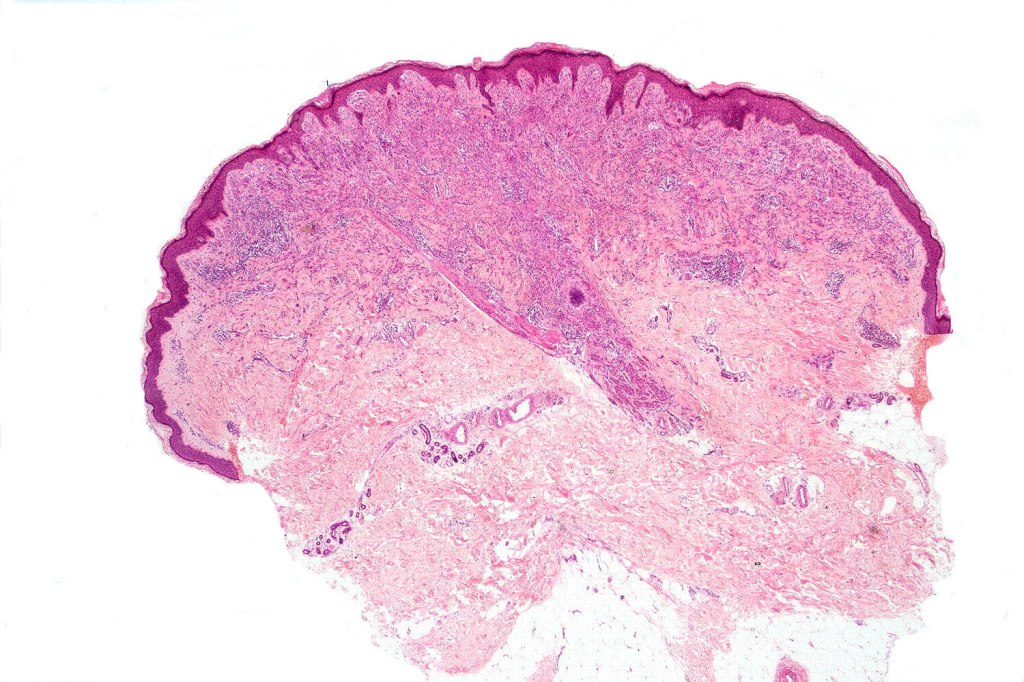

•Sharply circumscribed (begins and ends with a nest), symmetrical dome-shaped lesion. Symmetry is both horizontal and vertical (see image below)

•Wedge-shaped with the base uppermost or sometimes plaque-shaped silhouette

•Matures with depth-often best recognized at scanning/low power magnification & readily confirmed with S100 or MART1

•Maturation implies nest size and cell size diminishing with depth, at the base, the infiltrate may have a single cell infiltrating pattern